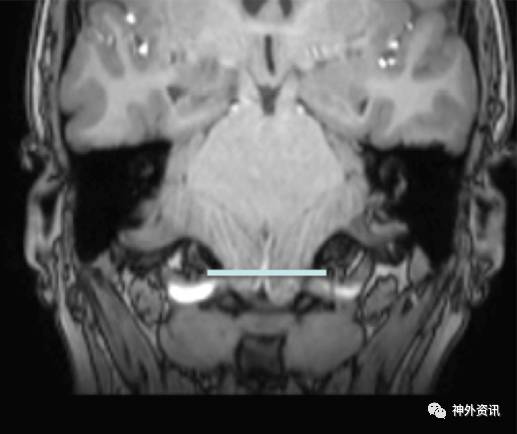

作者回顾性分析50例诊断为Chiari I型畸形的小儿患者,年龄2-21岁,平均9.3岁。在MRI矢状位和冠状位上测量和比较小脑扁桃体下疝情况(图1、2、3、4)。

图2. MRI冠状位图像,无小脑扁桃体下疝。

50例患儿中,48例在MRI冠状位发现小脑扁桃体不对称,左侧扁桃体下疝最大值为20.9毫米,右侧扁桃体下疝最大值为17.4毫米。MRI矢状位上,小脑扁桃体下疝范围从5-27.4毫米不等。5例(10%)患儿在MRI冠状位发现双侧小脑扁桃体下疝至枕骨大孔下长度小于3毫米,19例(38%)在冠状位上一侧小脑扁桃体下疝小于3毫米。但在MRI矢状位上扁桃体下移都超过3毫米,而每例患儿在MRI正中矢状位上的小脑扁桃体下疝均大于3毫米。作者依据测量的结果认为,Chiari I型畸形常常是不对称的小脑扁桃体下疝。如果仅在MRI正中矢状位上测量,小脑扁桃体下疝可能会造成误诊。因此,不应采用单一的MRI矢状位成像诊断Chiari I型畸形小脑扁桃体下疝的程度。